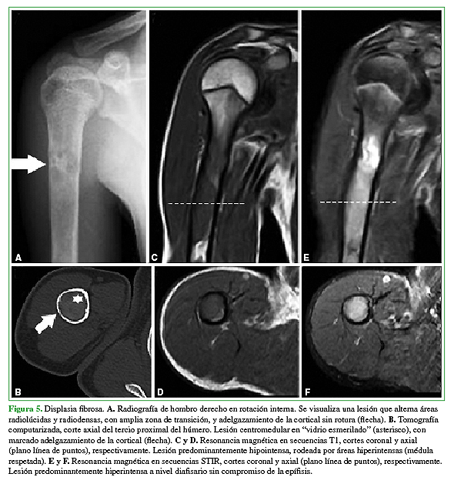

Los diagnósticos diferenciales más frecuentes son focos de hiperplasia de médula ósea grasa, displasia fibrosa (Figura 5), quiste óseo simple o aneurismático (Figura 6), lesiones condrales (encondroma, condrosarcoma) (Figura 7), infarto óseo antiguo, necrosis avascular (Figura 8) y fibroma condromixoide (Figura 9).